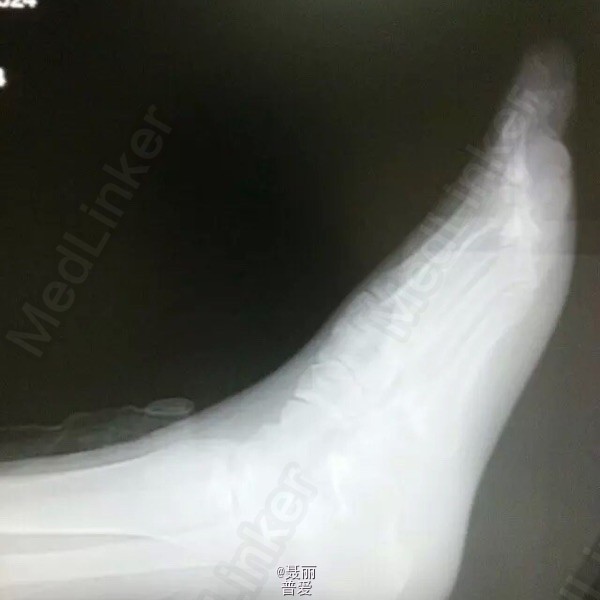

患者,女,39岁。扭伤致右足疼痛伴活动受限4月余。 患者于4月余前扭伤伤及右足,当即感右足外侧疼痛,下地活动行走时无力,活动受限。在我院行X线片提示“右足骰状骨撕脱性骨折”,行石膏固定,拆除石膏后行走仍有不适感,现来我院以求进一步诊治,门诊查体阅片后以“右足骰状骨撕脱性骨折”收住我科。 自受伤以来,患者神清,饮食睡眠欠佳,大、小便正常,体力下降,体重无明显改变。 既往史:“盆腔炎”病史,有“失眠”症状,否认“青霉素”及“头孢”过敏,

体格检查:T36.5℃ P 84次/分 R 21次/分 BP 130/73mmHg,神志清醒,平静面容,查体合作。发育正常,全身皮肤未见黄染,浅表淋巴结未及肿大,头颅无畸形,双侧瞳孔等大等圆,光反射灵敏。颈软,胸廓无畸形,双肺呼吸音清晰,未闻及干湿性啰音。心律齐,各瓣膜听诊区无杂音。腹平软,无压痛反跳痛,脊柱无畸形,各棘突无压痛。 专科情况:右足外侧Ⅰ度肿胀,轻度压痛,内翻应力试验阳性,前足扭转试验阳性,足背动脉搏动良好,右足各趾感觉、活动及末梢血运正常。 门诊资料:我院X线(10.24.253834)示:“右足骰状骨撕脱性骨折”。

初步诊断:右足骰状骨撕脱性骨折 诊疗计划:1.患肢抬高,消肿对症支持治疗。 2.完善相关检查(血、尿分析、肝肾功能、ECG等)。、卧床休息,不下地患肢负重活动。2、在医生指导下进行患肢功能锻炼。

患者未行手术治疗,石膏外固定,四个礼拜后来医院复查,嘱咐患者不负重,卧床休息,